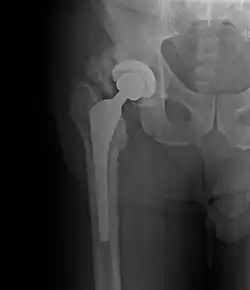

| Heterotopic ossification around the hip joint in a patient who has undergone hip arthroplasty |

Heterotopic ossification of varying severity can be caused by surgery or trauma to the hips and legs. About every third patient who has total hip arthroplasty (joint replacement) or a severe fracture of the long bones of the lower leg will develop heterotopic ossification, but is uncommonly symptomatic. Between 50% and 90% of patients who developed heterotopic ossification following a previous hip arthroplasty will develop additional heterotopic ossification.

Heterotopic ossification often develops in patients with traumatic brain or spinal cord injuries, other severe neurologic disorders or severe burns, most commonly around the hips. The mechanism is unknown. This may account for the clinical impression that traumatic brain injuries cause accelerated fracture healing.[2]